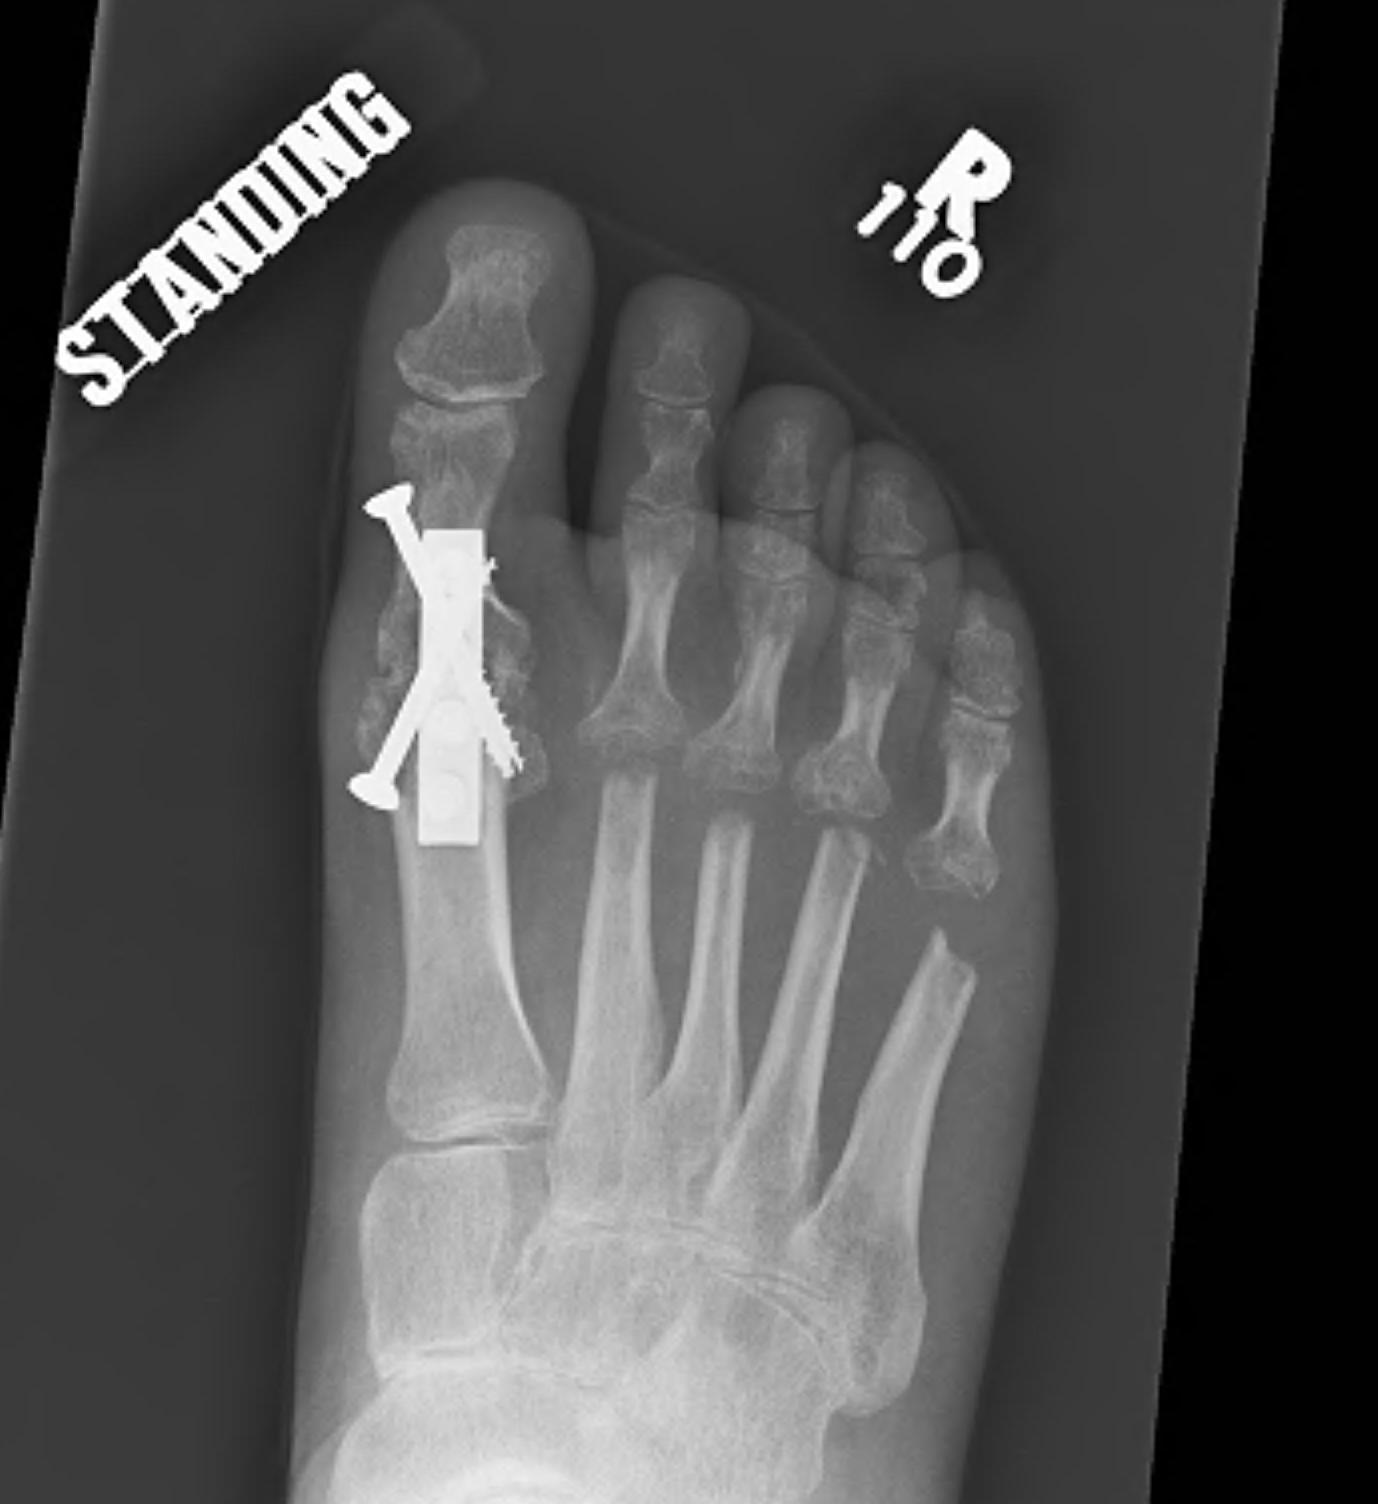

Hallux valgus / rigidus

Operative Options

Osteotomy / Arthrodesis / Arthroplasty / Keller's procedure (excision arthroplasty)

Dai et al Zhongguo Gu Shang 2012

- 1st MTPJ fusion in 129 feet with RA

- 3% nonunion

He et al J Foot Ankle Surg 2021

- systematic review of 1st MTPJ arthrodesis v arthroplasty in RA

- no difference in pain score, outcome, or reoperation rates

- complications of Keller procedure

- hallux valgus, cock up, flail toe

- reserve for salvage only